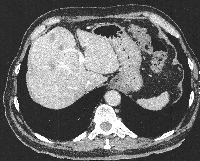

Πρόκειται για άνδρα ασθενή 67 ετών που διαπιστώθηκε ότι έπασχε από αδενοκαρκίνωμα του σιγμοειδούς με 6 συνολικά ηπατικές μεταστάσεις αμφοτερόπλευρα (εικόνες 1, 2). Η διενέργεια PET-CT δεν ανέδειξε εξωηπατική νόσο. Δεδομένου ότι ότι η πρωτοπαθής εστία δεν προκαλούσε αποφρακτικά φαινόμενα και εξαιτίας του εξαιρετικά μεγάλου καρκινικού φορτίου του ήπατος σε σχέση με αυτό το εντέρου, αποφασίστηκε η αντιμετώπιση πρώτα των μεταστάσεων ("liver first" approach). Σύμφωνα με την ανάλυση MeVis (εικόνα 3) η αριστερή ηπατεκτομή οδηγούσε σε 69% ηπατικό υπόλειμμα ενώ η αριστερή εκτεταμένη ηπατεκτομή οδηγούσε σε 28% ηπατικό υπόλειμμα (τριχασμός πυλαίας). Με βάση αυτά τα δεδομένα αποφασίστηκε η κάθαρση του ήπατος από το μεταστατικό φορτίο με ηπατεκτομή και σύγχρονη εστιακή καταστροφή με ραδιοσυχνότητες. Αρχικά, ο ασθενής υποβλήθηκε σε 8 κύκλους χημειοθεραπείας (Avastin, FOLFOX). Ακολούθησε αριστερή ηπατεκτομή, δύο σφηνοειδείς ηπατεκτομές (εικόνα 4) και εστιακή καταστροφή με ραδιοσυχνότητες του παρεγχύματος στο όριο των τμημάτων 5/8 (εικόνα 5), παρεμβάσεις που έφεραν την πλήρη κάθαρση του ηπατικού μεταστατικού φορτίου. Κατόπιν, ο ασθενής υποβλήθηκε σε ακόμα 4 κύκλους χημειοθεραπείας. Η ογκομέτρηση την 4η μετεγχειρητική εβδομάδα ήταν ικανοποιητική (εικόνα 6). Ακολούθως, ο ασθενής υποβλήθηκε σε σιγμοειδεκτομή. Τελικά, η χημειοθεραπεία ολοκληρώθηκε με άλλους 6 κύκλους. Ο ασθενής εξακολουθεί να παραμένει ελεύθερος νόσου στους τακτικούς ελέγχους (δις ετησίως) με κολονοσκοπήσεις και CT.